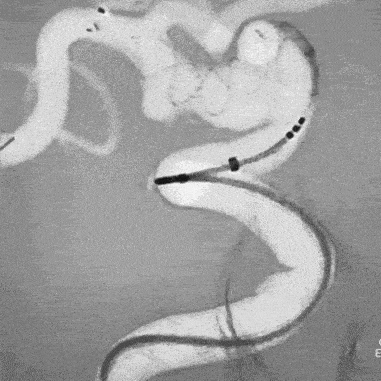

As part of the PENUMBRA SYSTEM, the Reperfusion Catheters and Separators are indicated for use in the revascularization of patients with acute ischemic stroke secondary to intracranial large vessel occlusive disease (within the internal carotid, middle cerebral – M1 and M2 segments, basilar, and vertebral arteries) within 8 hours of symptom onset. Patients who are ineligible for intravenous tissue plasminogen activator (IV t-PA) or who fail IV t-PA therapy are candidates for treatment.